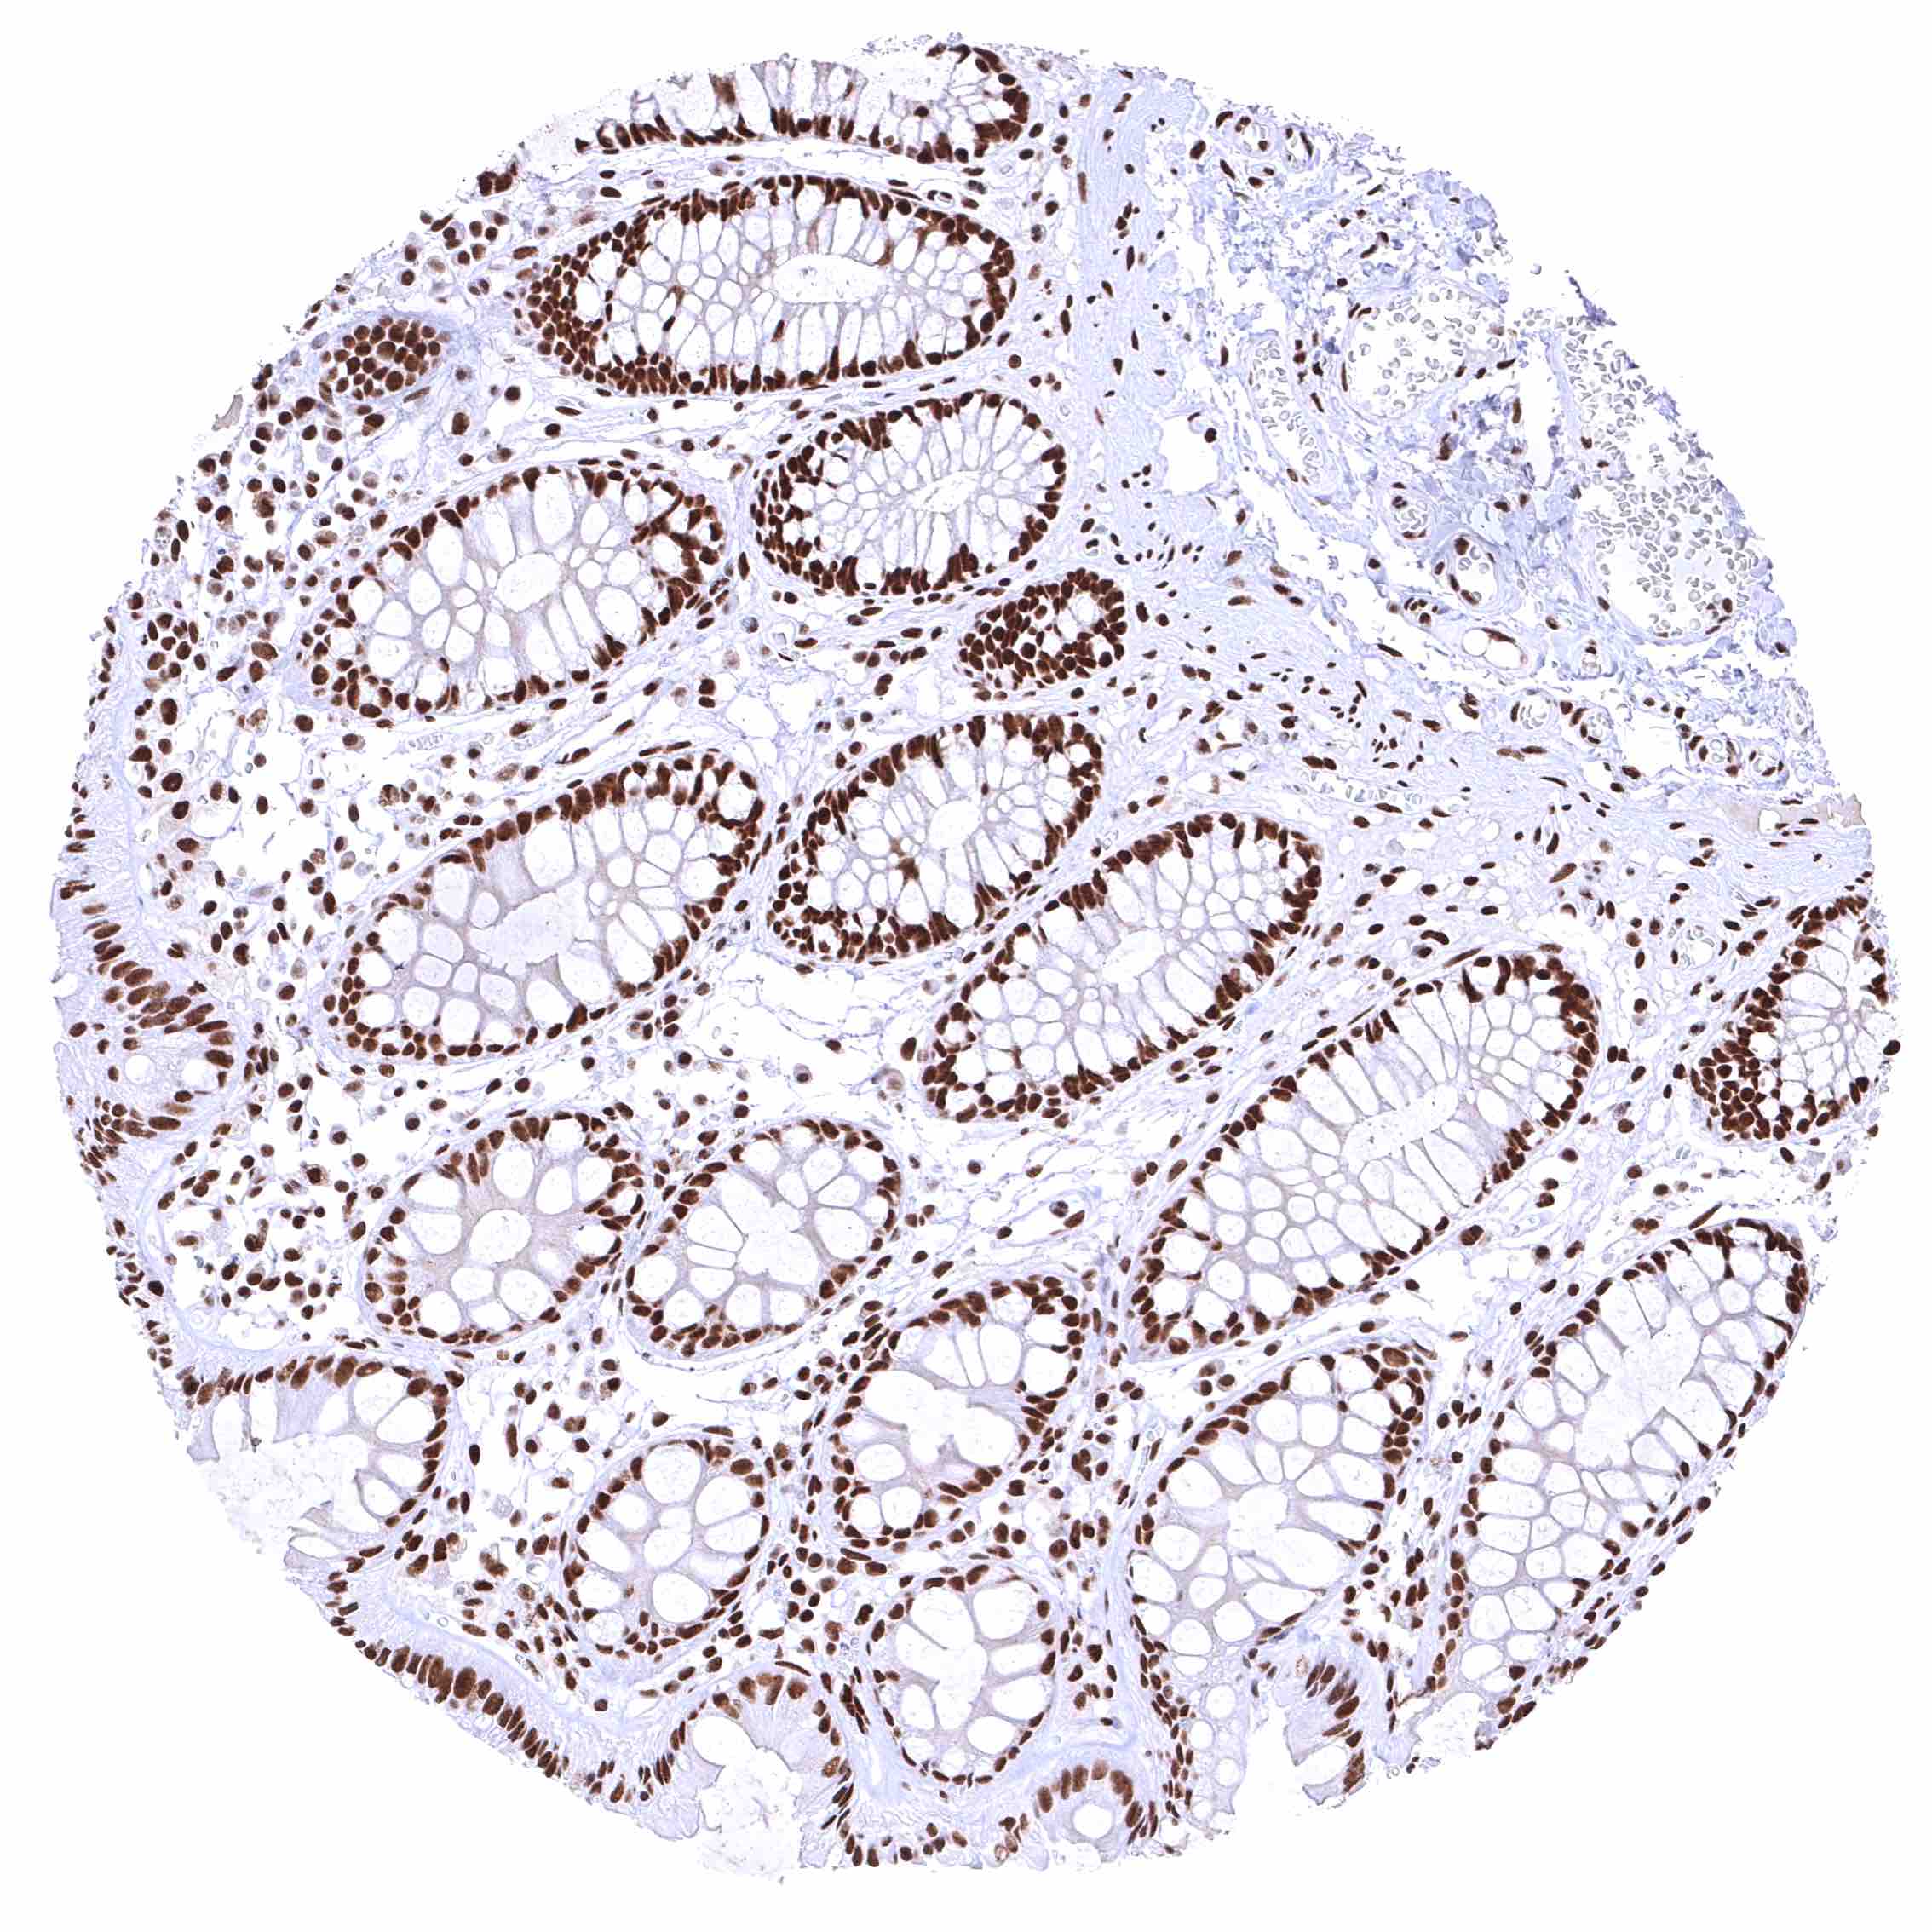

Rectum, mucosa – Nuclear BRD4 staining of surface epithelial cells is weaker than in crypts.